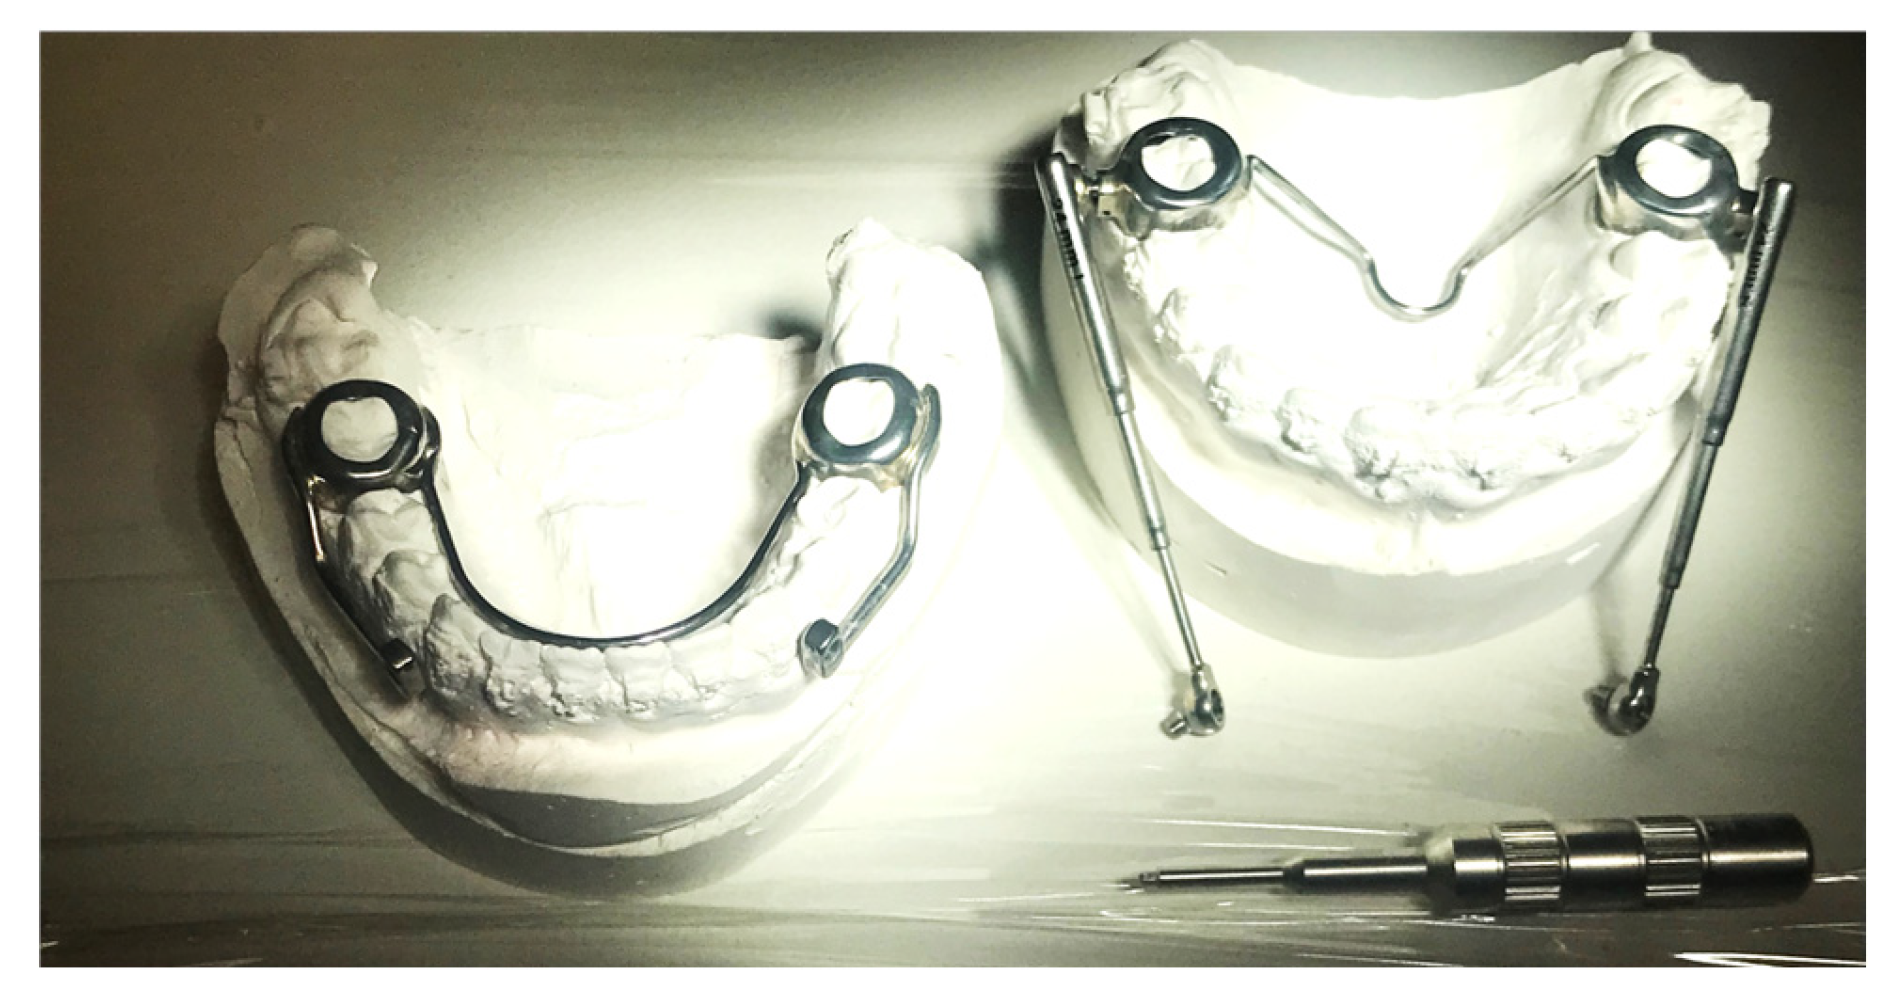

2.1. Simplified Design of the Herbst Appliance

| Traditional Design | Simplified Design | |

|---|---|---|

| Total number of bands per arch | 4 | 2 |

| First molar bands | Normal | Partial occlusal coverage |

| Goshgarin trans-palatal bar | Present | Present |

| Welded lingual arch | Present | Present |

| Welded arm extension from molar to first premolar | Present | Absent |

| Left and right telescopic tube | Present | Present |